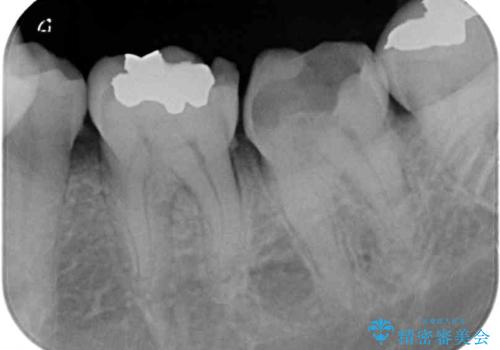

咬合力が著しく強いため、欠損の多い歯はフルジルコニアクラウンへ、その他の虫歯はゴールドインレー(PGAインレー)にて修復することとしました。

来院時は全てセラミックでの治療を希望されていましたが、歯列や咬み合わせから咬合力による破損リスクが高いと判断されたため、ゴールドインレーを選択しました。